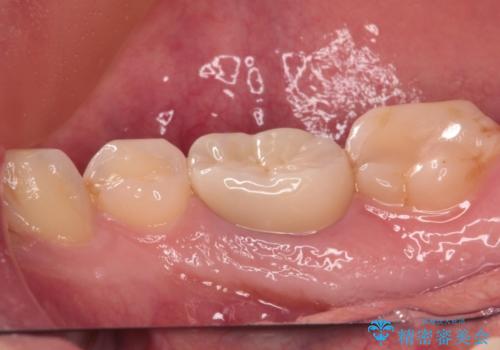

初診から2年以上が経過していますが、排膿路が再発することはなく、良好な状態を保っています。